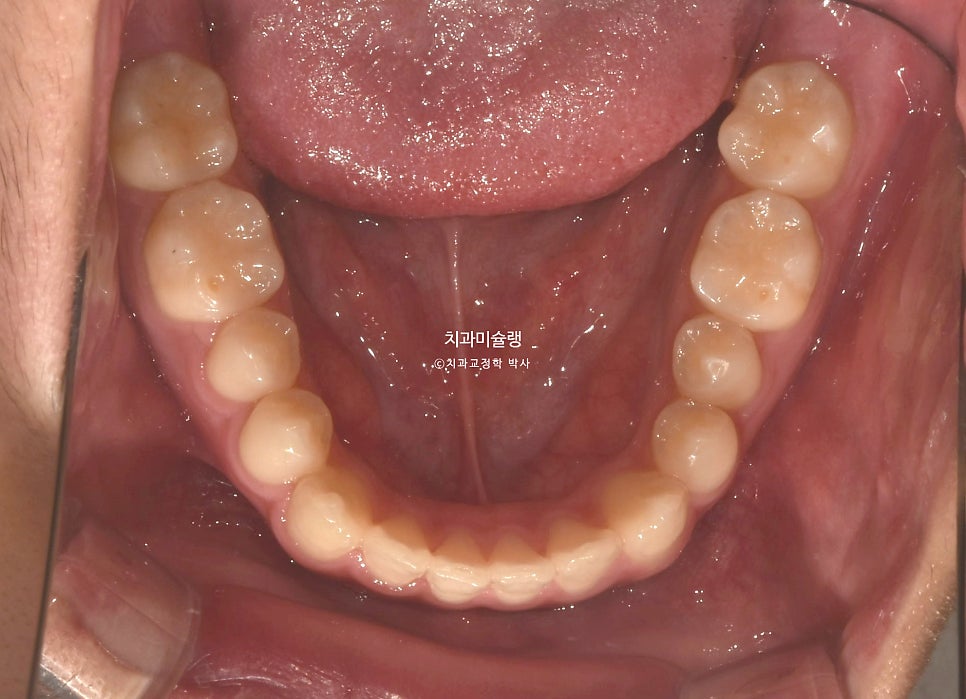

위 앞니가 벌어져있고 일부 개방교합이 보입니다.

어금니 교합관계는 3급이며 윗니가 아랫니를 덮지 못하는 절단교합 입니다.

치료계획은 아래 매복된 사랑니를 미리 발치하고 사랑니 공간으로 어금니를 순차적으로 이동시키는것.

유학생이라 봄, 여름. 겨울 방학때만 한번씩 내원 가능하여 인비절라인으로 치료키로 합니다.